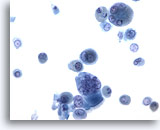

Figure 2

Bronchoalveolar lavage

Both macrophages and bronchial epithelial cells may be multinucleated. 40x

Bronchoalveolar lavage

Both macrophages and bronchial epithelial cells may be multinucleated. 40x

Figure 2

Bronchoalveolar lavage

Both macrophages and bronchial epithelial cells may be multinucleated.

40x

Bronchoalveolar lavage

Both macrophages and bronchial epithelial cells may be multinucleated.

40x